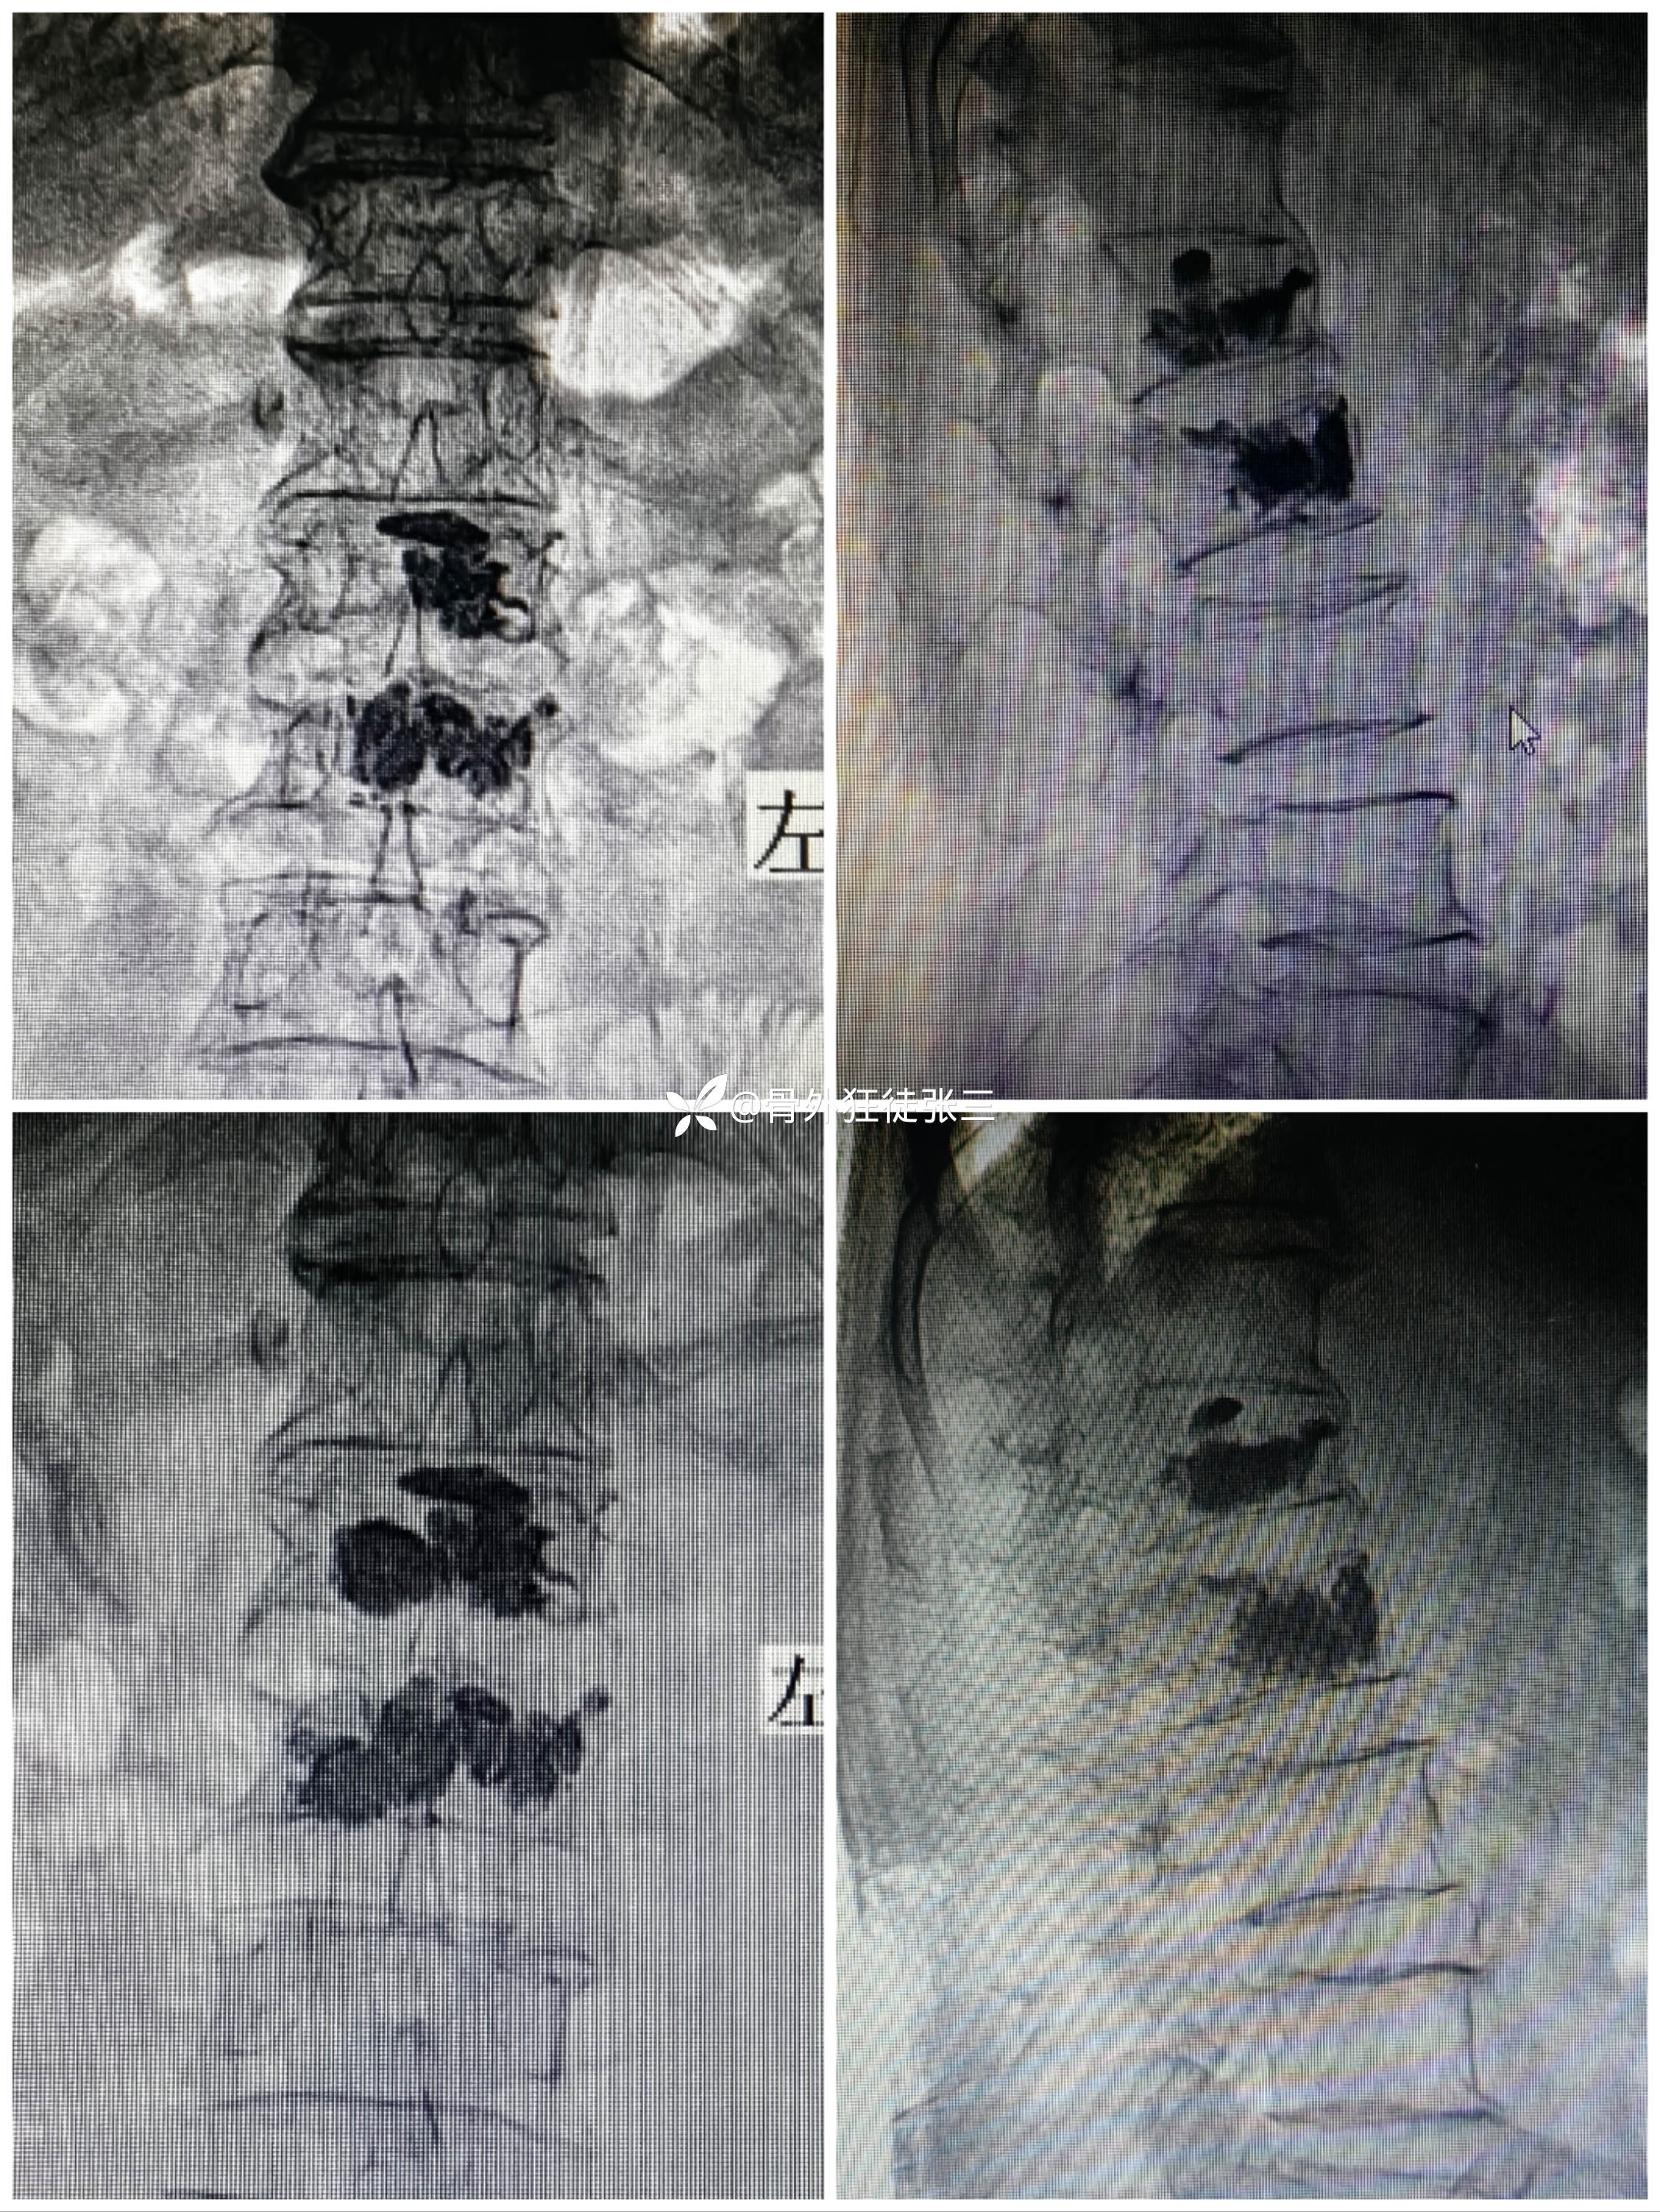

科室术前讨论后

考虑疼痛原因为骨水泥单侧弥散

再次行对侧穿刺,骨水泥置入

术后正位

术后侧位

术前术后对比